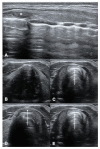

Airway management is a common and critical procedure in acute settings, such as the Emergency Department (ED) or Intensive Care Unit (ICU) of hospitals. Many of the traditional physical examination methods have limitations in airway assessment. Point-of-care ultrasound (POCUS) has emerged as a promising tool for airway management due to its familiarity, accessibility, safety, and non-invasive nature. It can assist physicians in identifying relevant anatomy of the upper airway with objective measurements of airway parameters, and it can guide airway interventions with dynamic real-time images. To date, ultrasound has been considered highly accurate for assessment of the difficult airway, confirmation of proper endotracheal intubation, prediction of post-extubation laryngeal edema, and preparation for cricothyrotomy by identifying the cricothyroid membrane. This review aims to provide a comprehensive overview of the key evidence on the use of ultrasound in airway management. Databases including PubMed and Embase were systematically searched. A search strategy using a combination of the term "ultrasound" combined with several search terms, i.e., "probe", "anatomy", "difficult airway", "endotracheal intubation", "laryngeal edema", and "cricothyrotomy" was performed. In conclusion, POCUS is a valuable tool with multiple applications ranging from pre- and post-intubation management. Clinicians should consider using POCUS in conjunction with traditional exam techniques to manage the airway more efficiently in the acute setting.